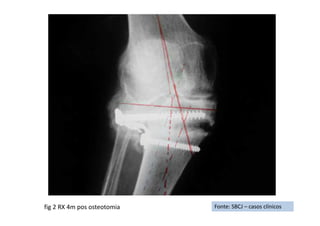

Fonte: SBCJ – casos clínicos

RX de Frente

RX de Perfil